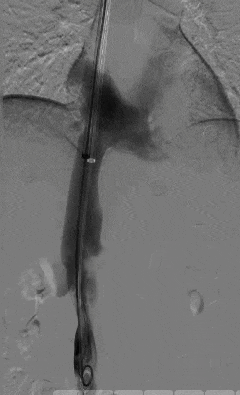

一切准备就绪后,田轩带领介入诊疗团队为阿婆实施下腔静脉滤器取出术。

术中,团队在影像设备的精准引导下,娴熟操作介入器械,精准定位倾斜的滤器,避开血管周边组织,逐步完成滤器的调整、抓取与取出操作。

整个手术过程十分顺利,未出现任何血管损伤等意外情况,这枚让阿婆和家属忧心许久的“困难”滤器被成功取出,术后阿婆生命体征平稳,身体状况良好。